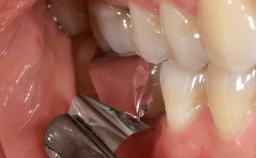

Due to their promising clinical performance, zirconia implants have recently become popular alternatives to titanium implants, particularly for areas with high esthetic demands (Holländer and coworkers 2016; Roehling and coworkers 2016; Lorenz and coworkers 2019). However, regardless of the reported high survival and success rates, zirconia implants were affected by peri-implant diseases over the short observation period, suggesting the importance of treating peri-implant diseases at zirconia implants (Becker and coworkers 2017). In their case, Frank Schwarz and Ausra Ramanauskaite present 3-year results following mechanical debridement alongside Er:YAG laser monotherapy.